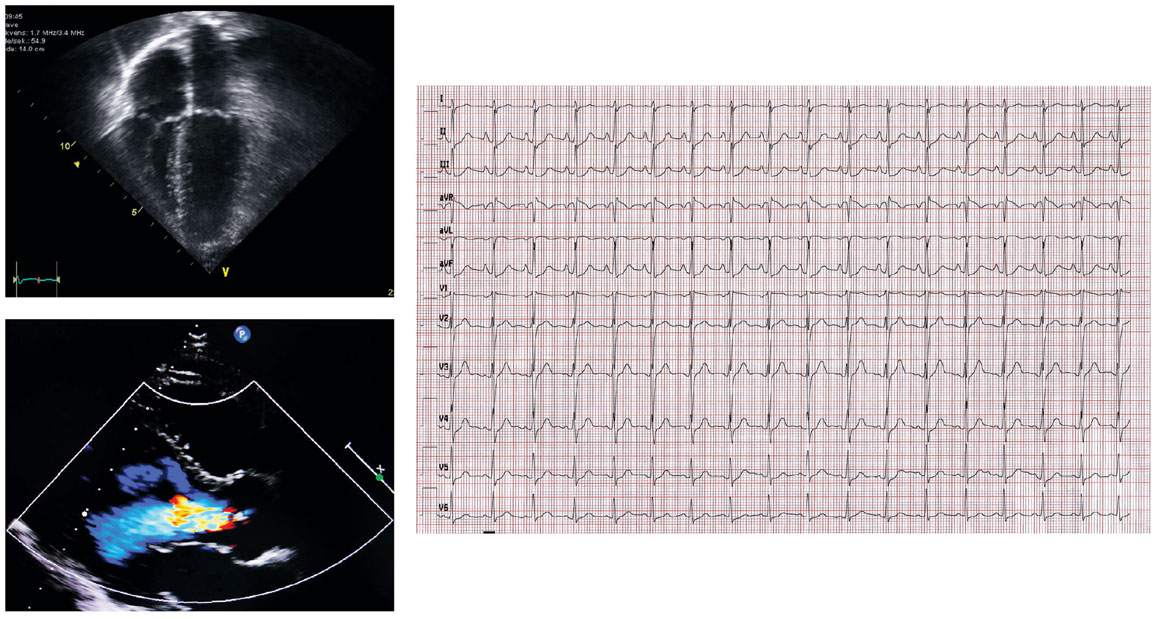

Diagnosing structural heart disease requires an echocardiogram—an ultrasound image of the heart and its blood flow. But that test is more expensive so fewer people receive it until they have developed more severe disease. A much more common test is the electrocardiogram (ECG)—the series of blips from heart electrical activity as it contracts, opens valves, and moves blood around. “There could be as many as several hundred million ECGs done in the world every year,” Poterucha says. “They can be done anywhere with almost no training, and they are inexpensive as far as medical tests go, so that gives it an enormous advantage.” Poterucha and his colleagues had already been working with AI deep learning models for other types of heart disease, so they wanted to see if they could train an AI neural network to take data from ECGs and predict which patients might be at high risk for structural heart disease and therefore should be recommended for an echocardiogram.